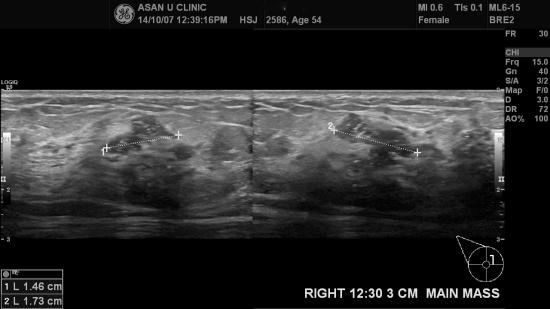

아산유외과 개원 후 159번째 유방암 진단

우측 유방에 몽우리가 만져져 내원하신 54세 여성입니다.

미세석회화가 동반된, 혹이 만져진다는 부위 외에도 한곳에 더 있었고

조직검사로 각각 침윤성 유관암으로 나왔으며

배경으로 상피내암이 넓게 분포되어 있습니다.

혹의 크기는 커도

침윤성 유관암의 가장 긴 길이로

병기가 결정되기에,

다행이 상피내암이 크게 깔려있는 것은 괴념치 않아도 됩니다.